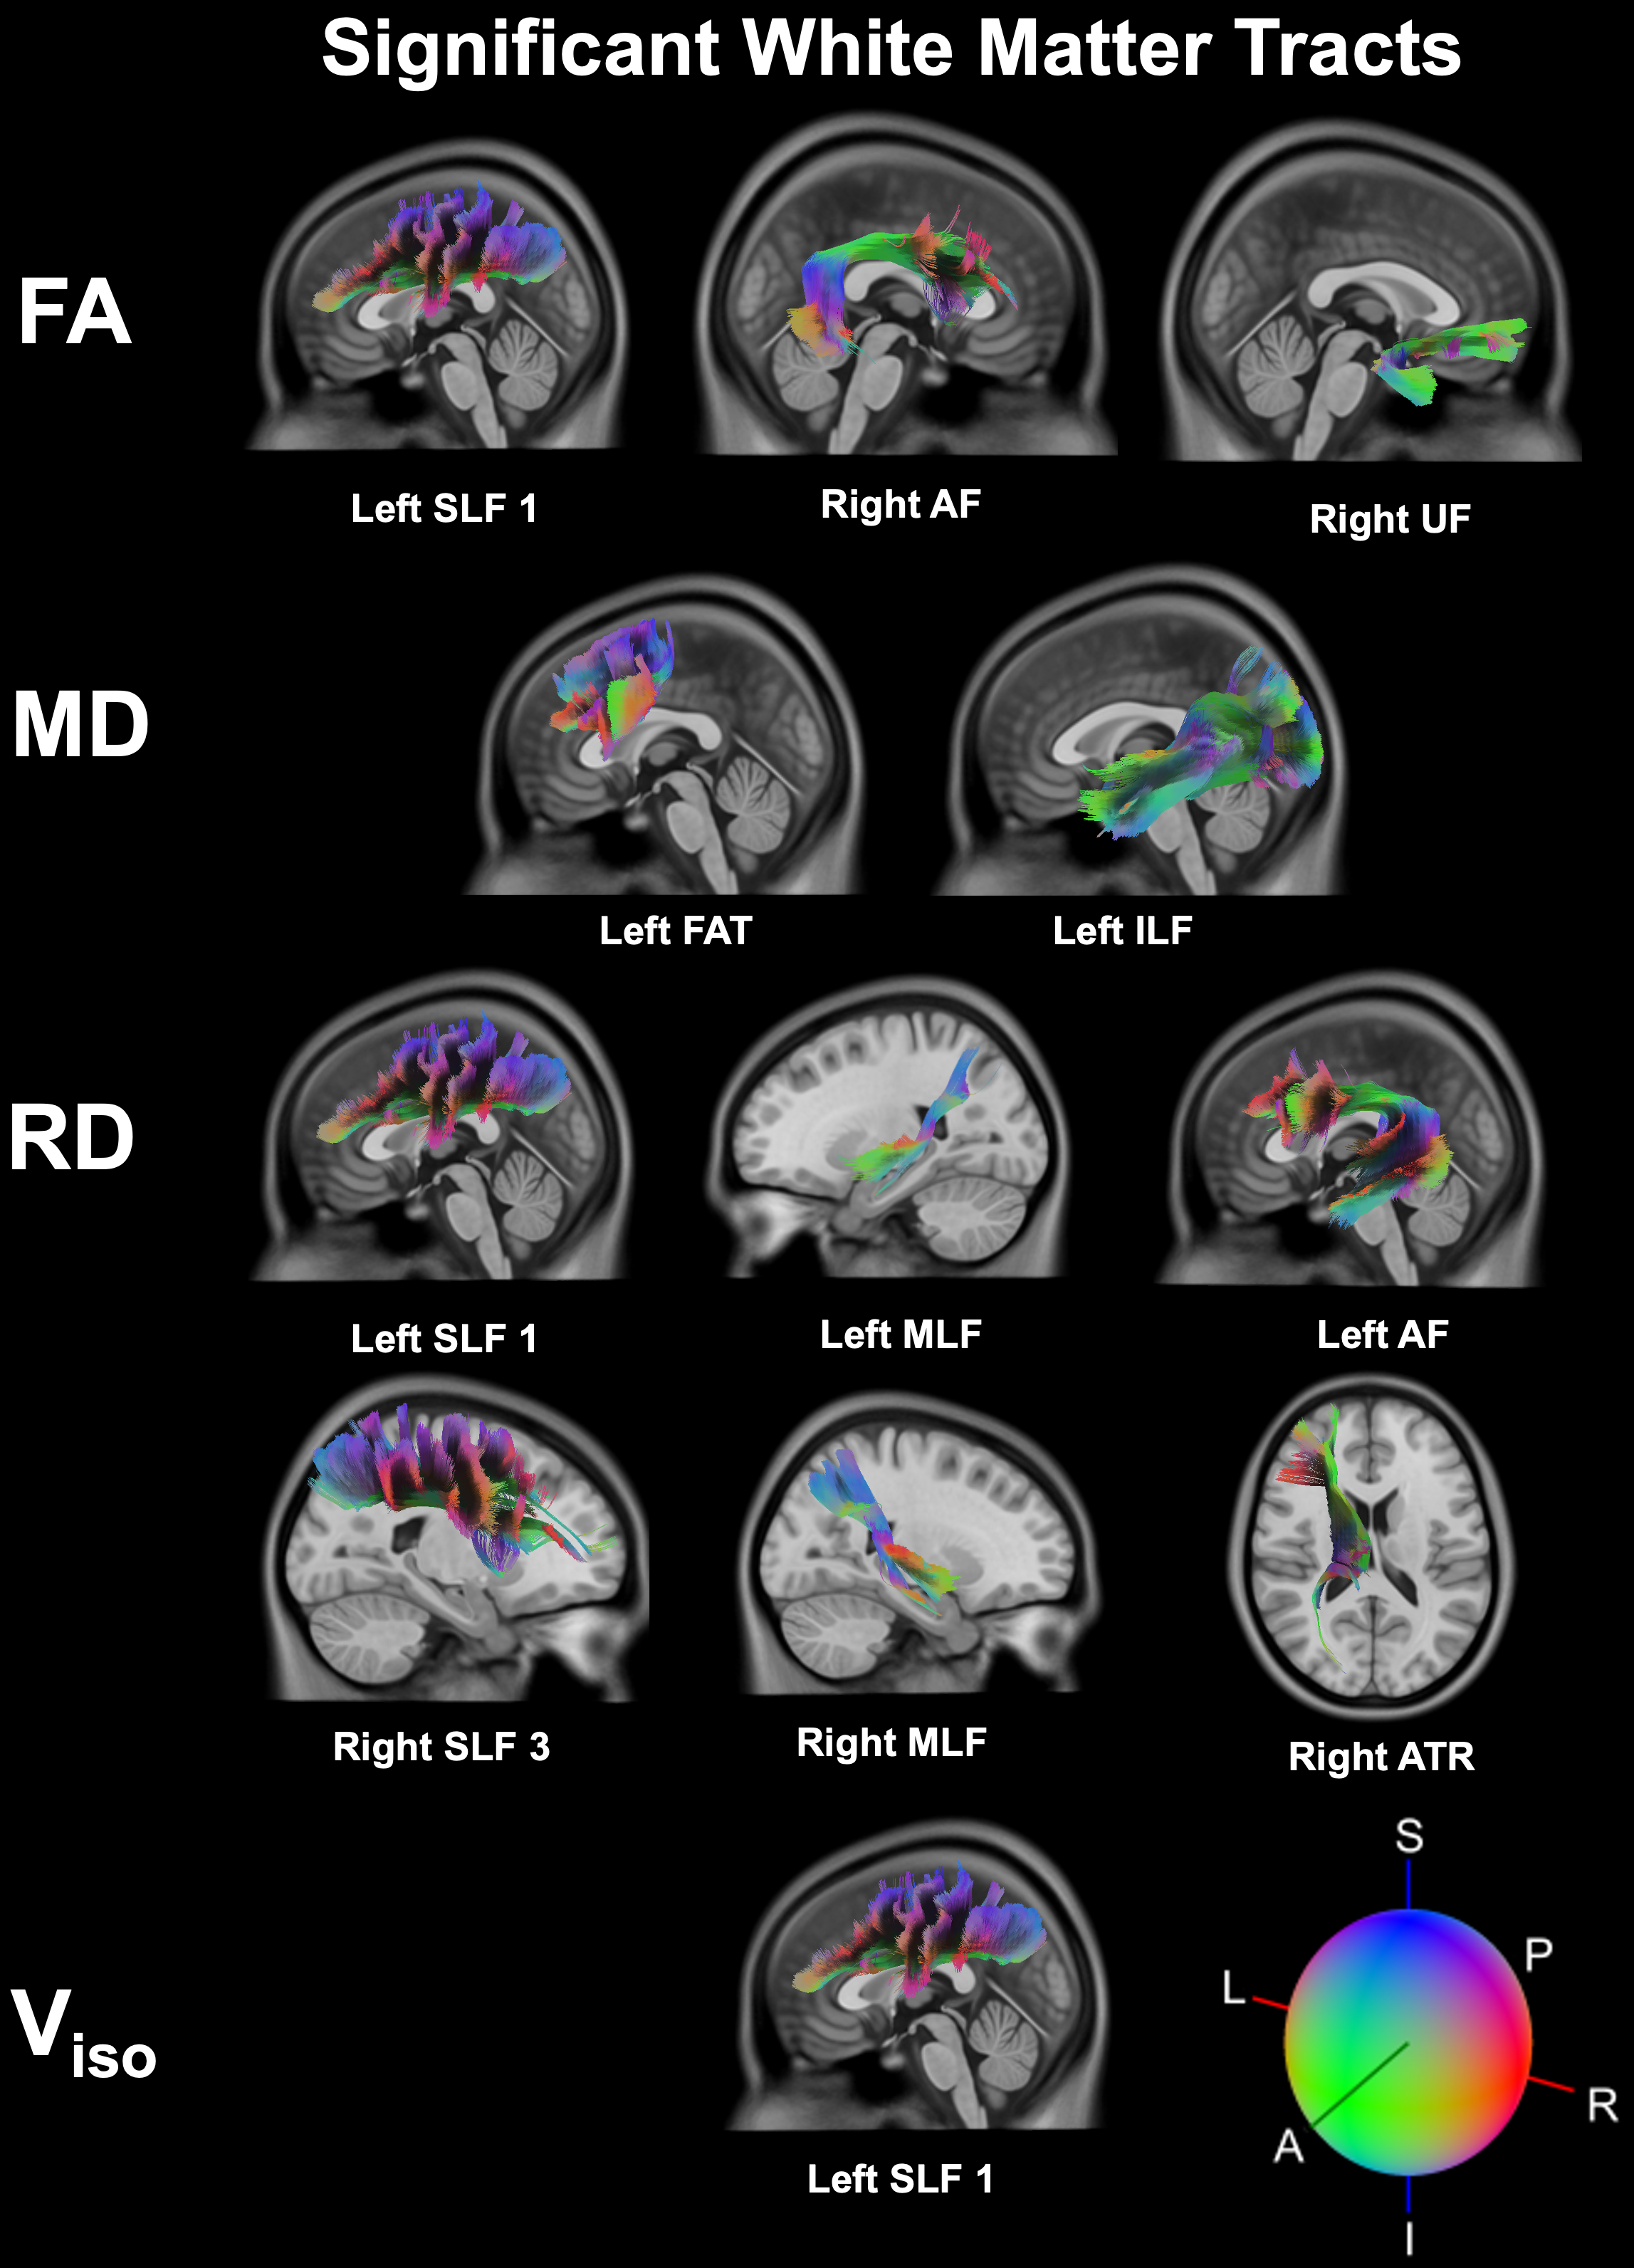

Sport-related concussion poses significant diagnostic challenges due to its subtle, transient nature and lack of identifiable biomarkers. To capture the changes from injury holistically, we integrated advanced neuroimaging with quantitative robotic assessment: Diffusion Tensor Imaging (DTI) and Neurite Orientation Dispersion and Density Imaging (NODDI) were used to detect acute microstructural white matter changes, while the Kinarm robotic platform objectively measured sensorimotor function via the Reverse Visually Guided Reaching (RVGR) task. This multimodal approach was applied to 12 concussed athletes (21 ± 2.1 y; 9 M/3 F; tested ~7 days post-injury) and 24 matched controls (21 ± 2.5 y; 11 M/16 F) to bridge structural and functional insights.

Significanttractswithsphere Noun slideshow grey Rvgrmethods

Behaviour (RVGR): Failed to detect functional deficits in the same acute period.

Screenshot 2025 05 30 at 11.49.38 pm

Neuroimaging (DTI/NODDI): Highly sensitive, revealing significant acute microstructural alterations in key white matter tracts.

Best correlation matrixnew page 0001

Conclusion

Our findings demonstrate that acute sport-related concussion induces detectable microstructural alterations in specific white matter tracts (↑FA, ↓MD/RD/Viso), yet these changes occur without concurrent deficits in sensorimotor performance on the precise Kinarm RVGR task. This critical disconnect underscores that advanced diffusion MRI (DTI/NODDI) is highly sensitive for detecting subclinical brain injury, revealing underlying pathology that standard functional assessments may miss. Consequently, relying solely on behavioural measures risks underestimating injury severity and compromising athlete safety. Multimodal assessment protocols, integrating both advanced neuroimaging and quantitative functional tools, are therefore essential for accurate diagnosis, informed return-to-play decisions, risk stratification, and targeted rehabilitation strategies following concussion.